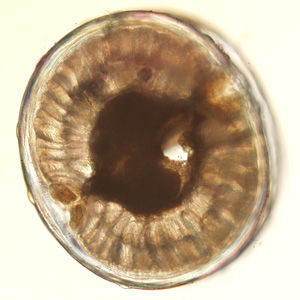

A 27-year-old man had worms excised from his eyelid and chest at a health care facility in Canada. The patient had traveled to Sudan two years earlier, but had not traveled since then. The worms were sent to the DPDx Team for diagnostic assistance. The worm which was removed from the eyelid (Figure A) measured 55 mm in length. Figures B-D show the anterior, middle, and posterior portions of the same worm, respectively, at 100x magnification. A thin cross-section was made with a scalpel at approximately mid-body and examined. Figures E and F show what was observed at 100x and 200x magnification, respectively, of the cross section. What is your diagnosis? Based on what criteria?

Figure E